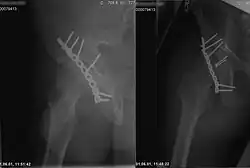

Röntgenaufnahme einer rechten Hüfte, Knochenbruch fixiert mit Lochblechstreifen und Senkkopfschrauben aus Metall, Operationsnaht verklammert